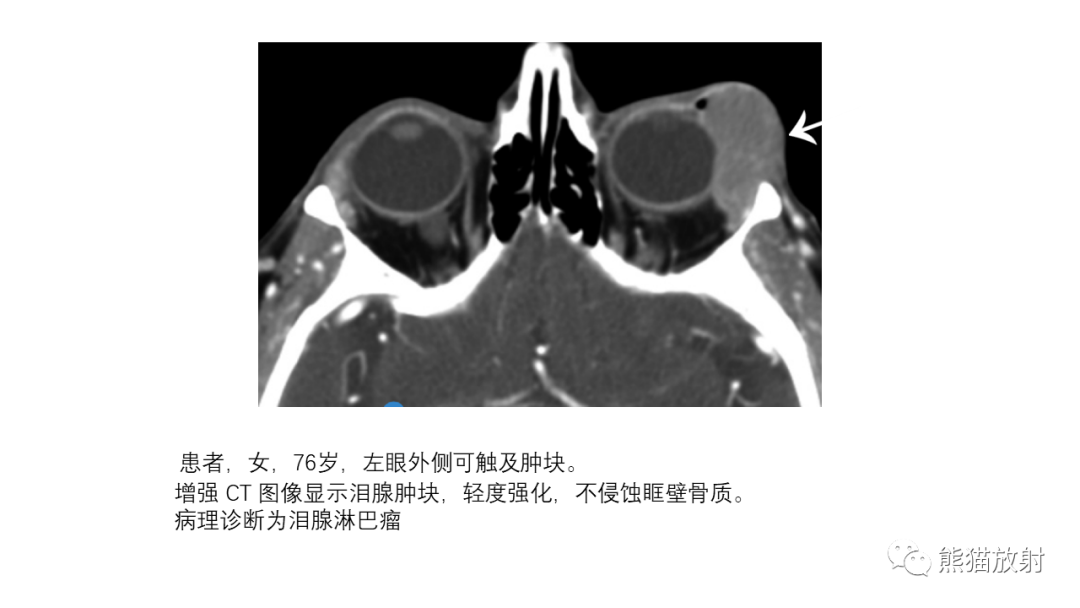

泪腺多形性腺瘤 VS 眼眶淋巴瘤